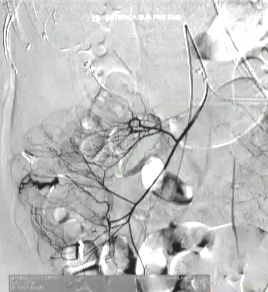

(1)操作流程·诊断性血管造影:用5F导管插管至肠系膜上/下动脉,寻找造影剂外溢(活动性出血)直接或间接征象 · · 超选择插管:通过同轴技术引入3F微导管,尽可能将导管送至直动脉(vasa recta) 或出血点最远端 · · 栓塞:首选微弹簧圈(2-3mm × 20-30mm),放置2-3个即可;也可用聚乙烯醇颗粒(>250μm);禁用液体栓塞剂(如酒精),因其肠坏死率高 · · 终点:造影证实外溢停止,同时保留近端和远端血流(不牺牲侧支循环) · (2)栓塞程度:多少算够?多少算多?理想情况:仅栓塞出血点所在的直动脉 若无法超选至直动脉,可栓塞边缘动脉(marginal artery),但必须确保:

o 近端和远端有足够的侧支血供

o 栓塞长度控制在3-4 cm以内(作者经验),避免过大范围缺血 o 栓塞的目标不是完全阻断血流,而是降低出血点的灌注压,配合局部血管痉挛和患者自身凝血能力形成血栓 5. 微导管远端栓塞临床数据:疗效与安全性一篇发表在2004年的文章汇总了12项研究【Brian Funaki 2004】、超过150例病例,核心数据如下: